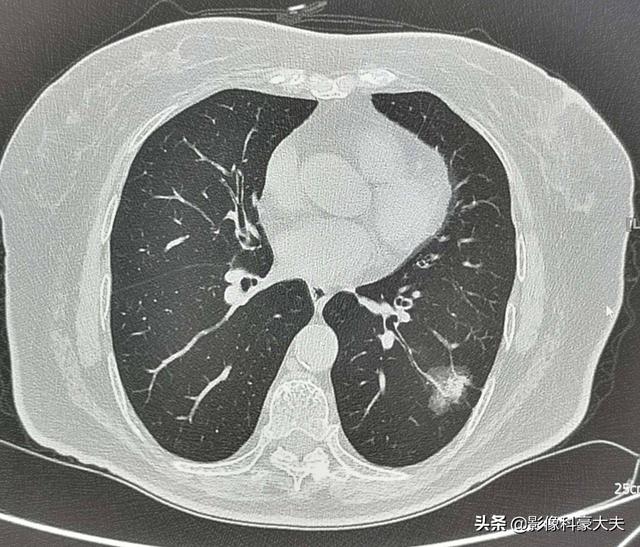

Bei dieser Frau mittleren Alters mit einem 2,2 cm großen Mischmembran-Glasknoten in der linken unteren Lunge handelt es sich beispielsweise um einen Hochrisikoknoten, der in der Tat die klassischen Anzeichen eines Lungenadenokarzinoms aufweist, zu denen gehörenGut ausgeprägter Mattigkeitsschatten mit Gefäßeintritt und Verdickung, bronchiales Insufflationszeichen, distale Pleurabeteiligung, chirurgische Pathologie eines invasiven LungenadenokarzinomsDiese Art von Läsion wird nicht zur Nachsorge empfohlen und sollte zur Abklärung weiter untersucht werden, um eine Metastasierung und eine verzögerte Behandlung zu vermeiden.